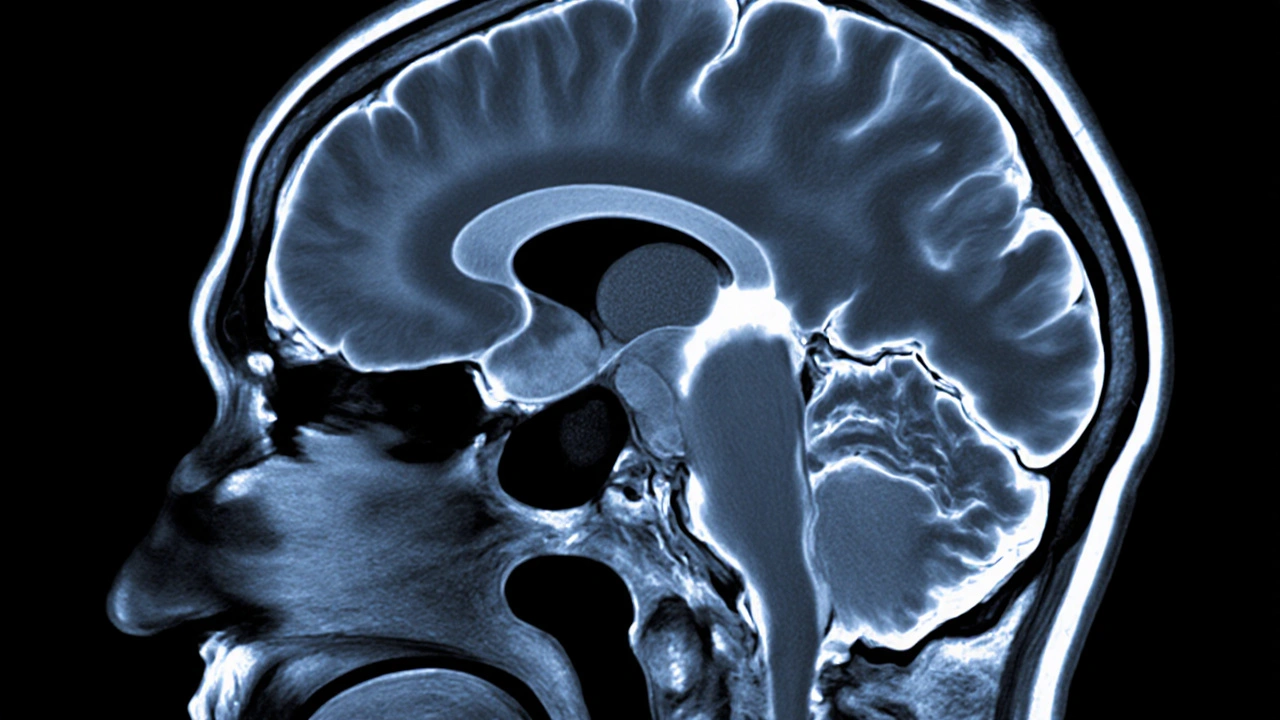

MRI of Brain‑Pituitary Region | Visualize structural causes | Absent or thinning posterior pituitary bright spot; tumor, infarct, or stalk compression visible. |

Is the MRI “bright spot” important?

Yes. On T1‑weighted images the posterior pituitary normally appears bright because of stored ADH. Its absence or reduction often signals central diabetes insipidus, especially when correlated with clinical findings.